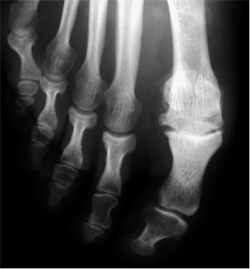

¿Qué es el hallux rígidus?

Es una limitación de la movilidad de la articulación metatarsofalángica del dedo gordo. Esta limitación altera el funcionamiento normal del pie y puede producir dolor. Cuando progresa, aparece una prominencia dorsal en esta articulación que puede ser muy dolorosa.

Hay muchos tipos de cirugía para tratar el hallux rígidus. Cada especialista tiene sus preferencias en función de su formación y experiencia. El hallux rígidus puede tener diferentes grados evolución. Dependiendo del grado evolutivo puede ser necesario: resección protuberancia, osteotomías (cortes) de los huesos o fijación de la articulación.